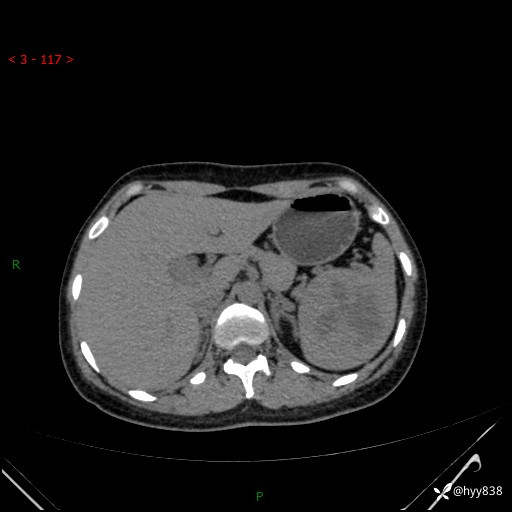

患者性别:男

患者年龄:44岁

主诉:外院超声发现脾脏占位,来我院进一步诊治。

辅助检查:CT

临床诊断:脾脏占位

脾脏CT平扫+增强(动脉期+静脉期)